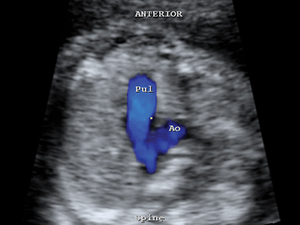

Aortic outflow tract with colour indicating the flow

Colour flow of both pulmonary artery and aorta Limps